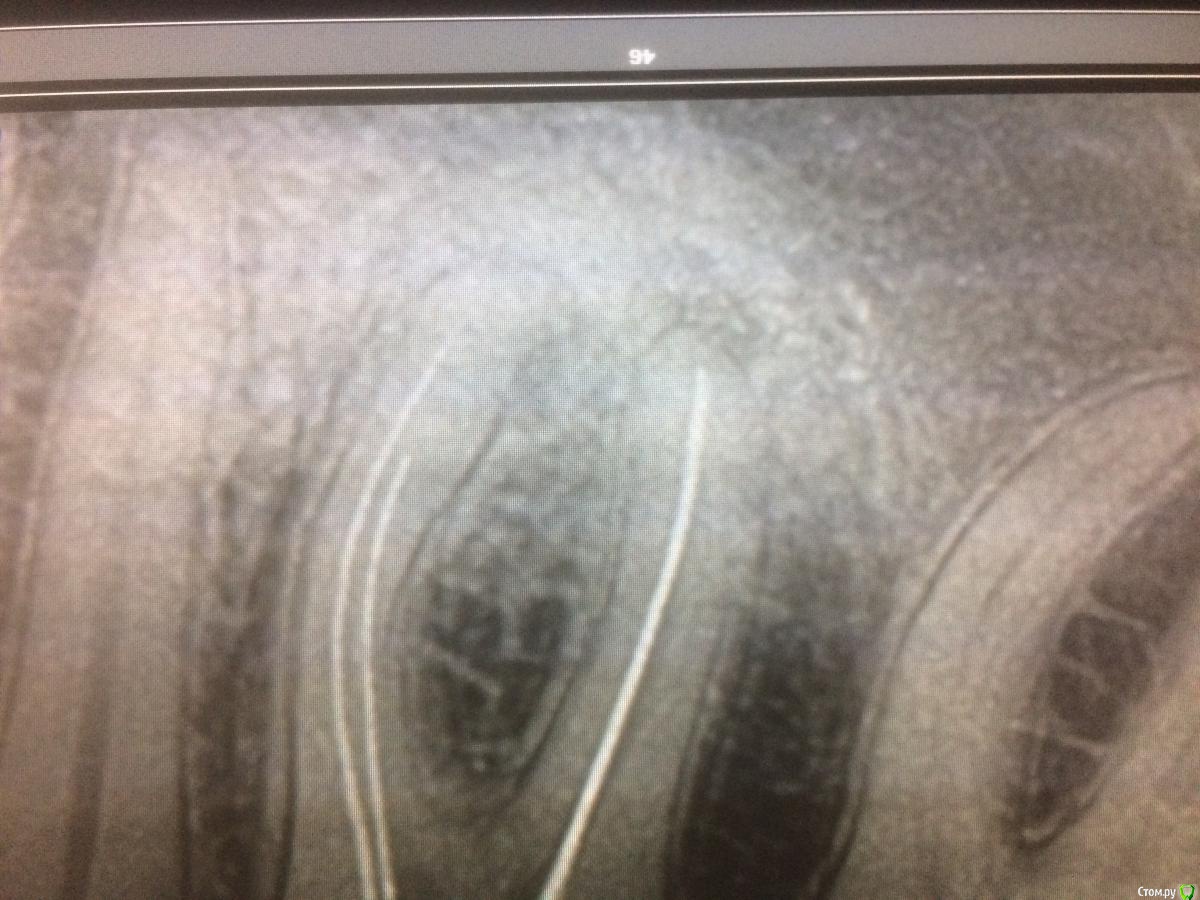

xMeDx Опубликовано 31 июля, 2019 Поделиться Опубликовано 31 июля, 2019 Начальная ситуация :пациент жалуется на застревание пиши между 4.5,4.6.Делаю снимок 4.6-большая пломба и слегка прикрыты устья дистального канала материалом а так канал пустой .Медиальные запломбированы на половину .Пломбировка рыхлая .На апексах легкое разряжение костной ткани.Легкая боль при перкуссии. Распломбировал,обработал химически.На неделю кальций и временная пломба.Через 5 дней пациент приходит с жалобами на ноющие боли которые особо и не беспокоят но спать не дают и обезболивающее 2 раза в день (это со слов пациента жалобы ).Открываю каналы.Обрабатываю .Закрываю постоянным тиэдент +гутта.Назначаю нпвс.Это вчера.Сегодня зуб болит так же.Причина просто реакция на кальций и нужно время или может быть что-то ещё ? Ссылка на комментарий

xMeDx Опубликовано 31 июля, 2019 Автор Поделиться Опубликовано 31 июля, 2019 покажите снимокСмущает ещё близость нижнечелюстного канала 1 Ссылка на комментарий

vse32 Опубликовано 31 июля, 2019 Поделиться Опубликовано 31 июля, 2019 Смущает ещё близость нижнечелюстного канала До нч канала там еще как до Канадской границы. Близость канала может смущать хирурга при травматичном удалении или терапевта если он делает очень большой овертритмент.Канал во всех этих случаев болей не даст, а вот повреждение нерва в канале даст онемение. Временное или постоянное. Зависит от характера травмы.Про коффер, качество и прочее промолчу. У каждого свое, я так понимаю Вы врач начинающий. Научитесь еще. Главное форум почаще читайте и не бойтесь задавать глупые вопросы, а так же получать на них не всегда приятные ответы. Ну а по существу вопроса. Любая боль после эндодонтического вмешательства это результат проникновения чего либо за апекс.1. Механическая причина - оверинструментация даже на 1 мм может дать боль. Вспоминаем. Апекс это не рентгологическая верхушка корня, апекс чуть раньше. И выводя инструмент до рентгенологической верхушки Вы уже сделали оверинструментацию.2. Химико-биологическая причина. а) Проталкивание за апекс содержимого канала. б) Вывод любого материала (силлер, кальций, пульпосептин) - это все может вызвать реакцию периодонта. Эти вещества там лишние. в) Проникновение ирриганта. - смотри пункт б)Все это вызывает обострение процесса, но если канал был качественно обработан механически, медикаментозно и впоследствии хорошо обтурирован - все пройдет. 6 Ссылка на комментарий